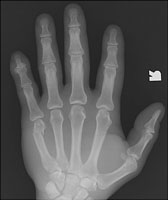

So named because of the common occurrence in prizefighters, the fracture involves the distal metacarpal neck, usually of digit five. The distal fracture fragment is volarly angulated and may be externally rotated. The injury results from direct trauma to the hand.

- Click on the image for a larger versionBOblique radiograph of the hand. This confirms the volar displacement of the distal fracture fragment.